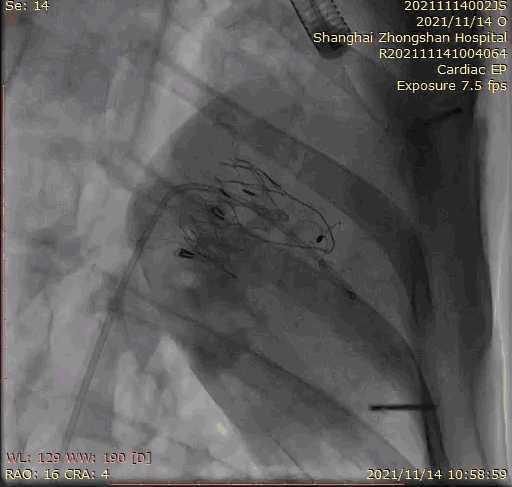

本次臨床前研究經(jīng)右側(cè)頸靜脈置入LuX-Valve Plus輸送系統(tǒng)可調(diào)彎鞘管,在DSA及超聲引導(dǎo)下將人工三尖瓣瓣膜植入到原有三尖瓣位置,利用獨(dú)特的錨定技術(shù)將人工瓣膜支架可靠固定在預(yù)定的位置。

上海中山醫(yī)院葛均波院士、錢菊英院長、周達(dá)新教授、潘文志教授、潘翠珍教授、李偉教授共同完成此次臨床前研究。術(shù)后葛均波院士對(duì)Lux-Valve Plus的器械操作性能給予了高度評(píng)價(jià),DSA和超聲影像也顯示出在本次研究中Lux-Valve Plus的安全性和有效性俱佳。

Lux-Valve是全球第一款具有我國完全自主知識(shí)產(chǎn)權(quán)的經(jīng)導(dǎo)管介入三尖瓣置換系統(tǒng),利用前瓣夾持及室間隔錨定的復(fù)合方式進(jìn)行瓣膜裝置的固定,不依賴瓣環(huán)徑向支撐力,同時(shí)采用自適應(yīng)復(fù)合裙邊材料,有效的貼合密封柔軟的三尖瓣瓣環(huán),針對(duì)于三尖瓣返流的患者有優(yōu)異的療效。Lux-Valve Plus采用全新的經(jīng)血管輸送系統(tǒng),經(jīng)頸靜脈入路創(chuàng)傷更小,可以進(jìn)一步降低手術(shù)風(fēng)險(xiǎn)。相信在后期正式臨床研究開展中,Lux-Valve Plus必定會(huì)為更多的三尖瓣反流患者帶來福音。